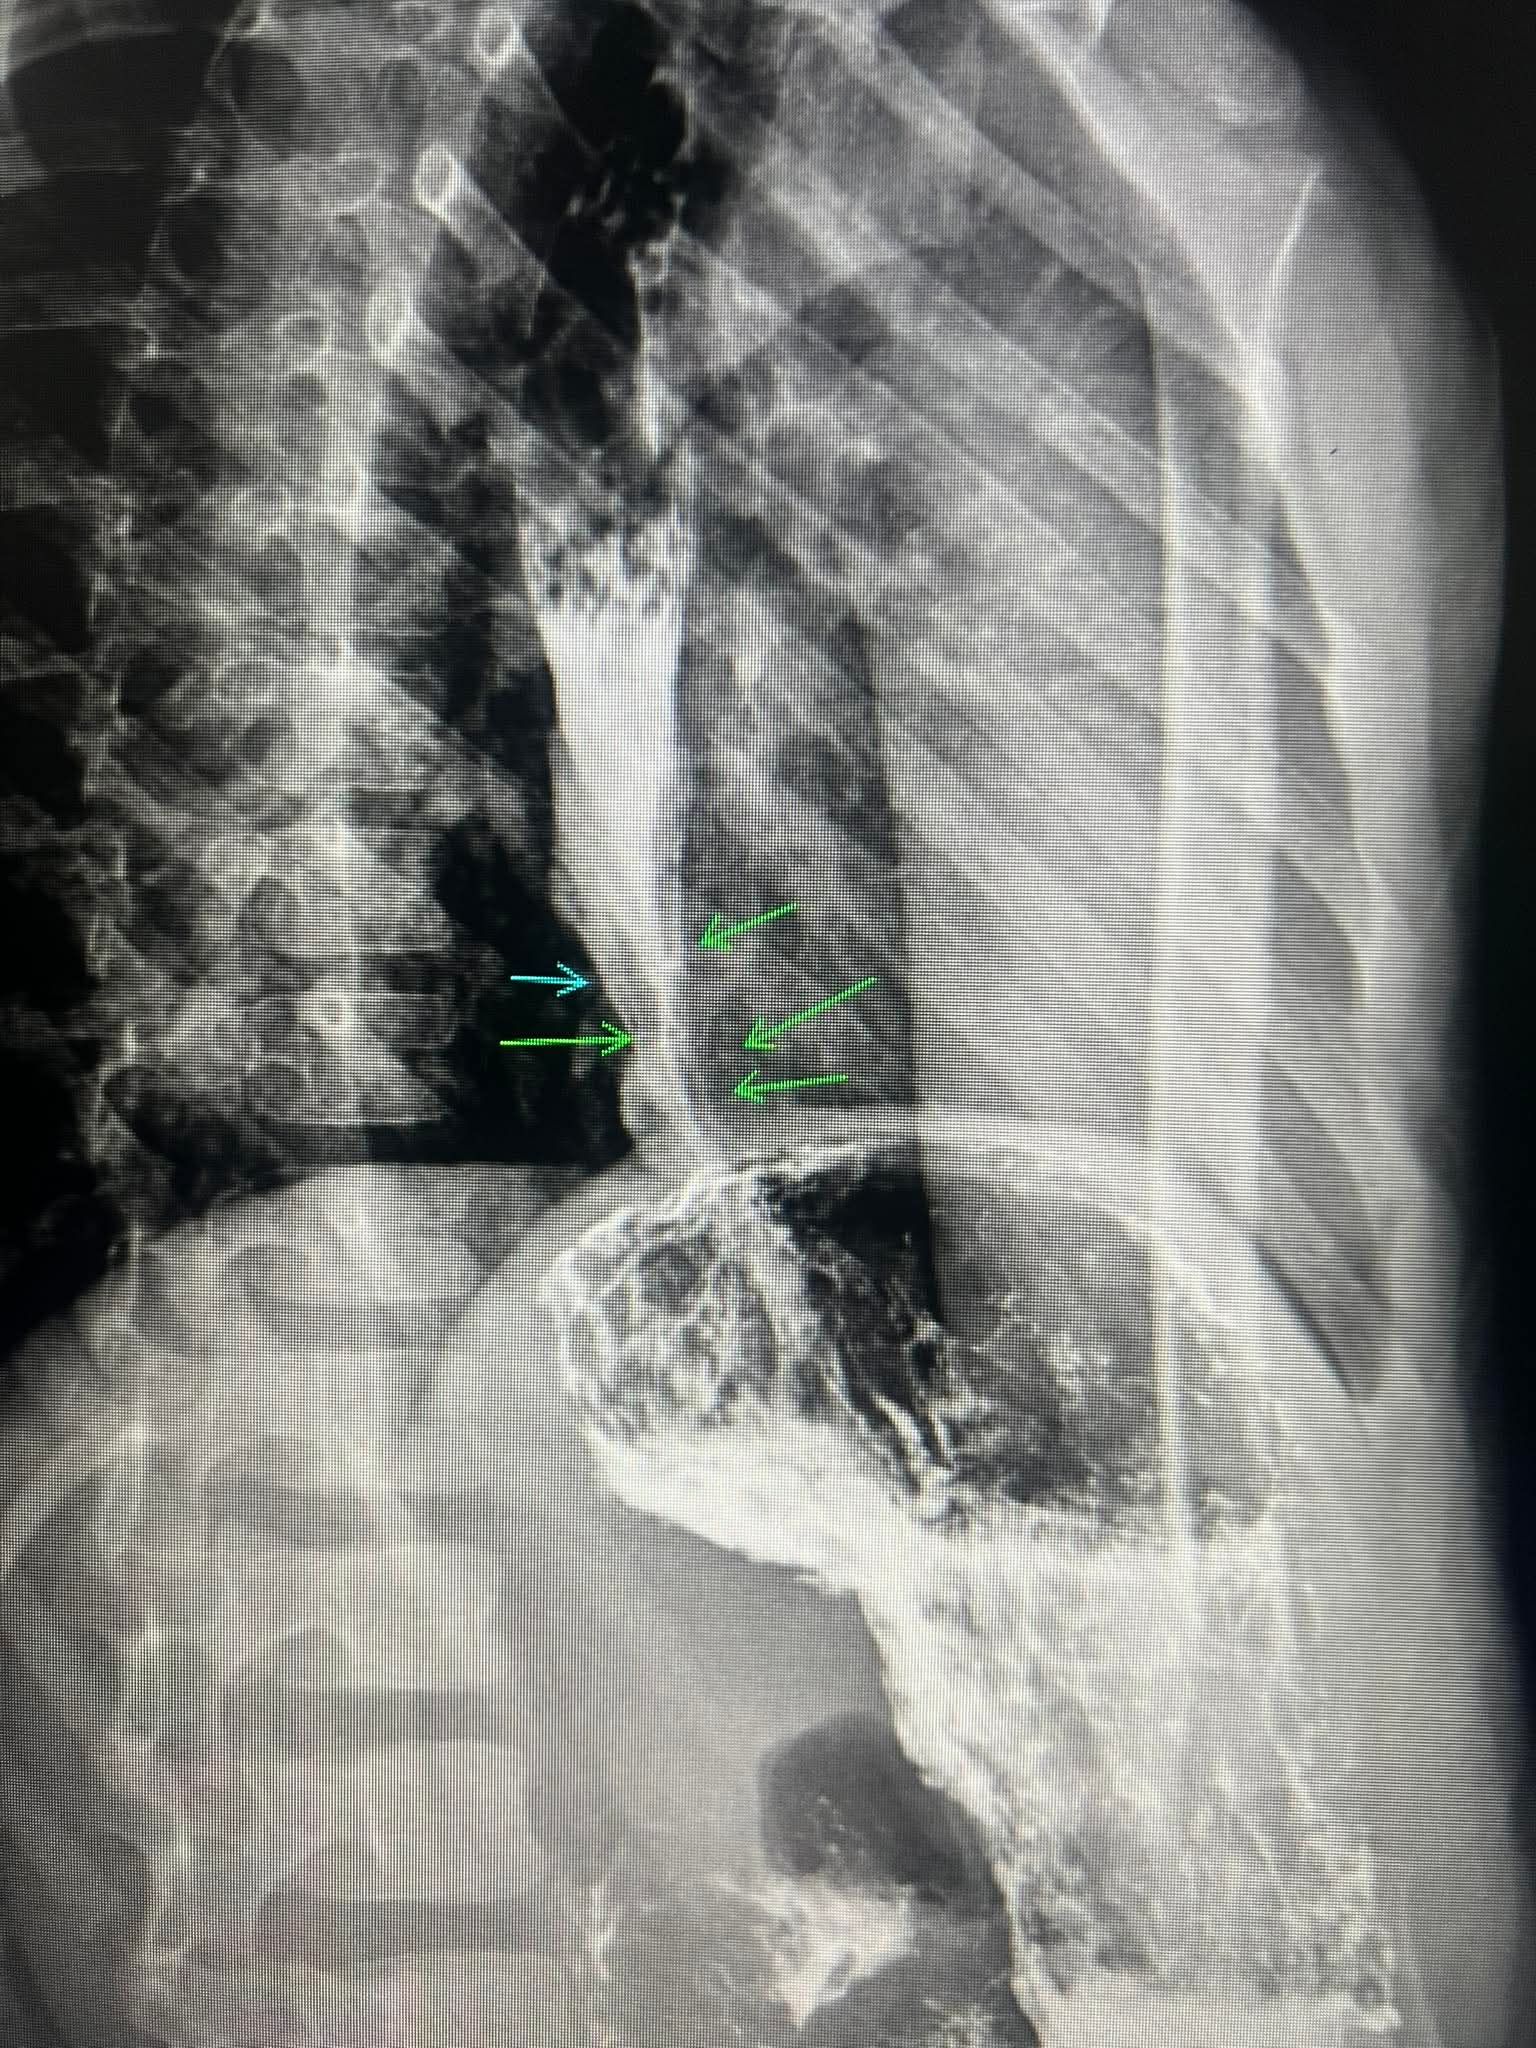

"Qida borusu yanıb, çapıqlaşıb, daralıb, sonradan dəfələrlə bujlama proseduru nəticəsində darlıq aradan qalxıb. Lakin çapıq deformasiyası və bu səbəbdən qida borusu qısaldığına görə həm də yırtıq yaranıb. Kimyəvi aşılayıcı maddələri uşaqların əli çatmayan yerlərə qoyun".